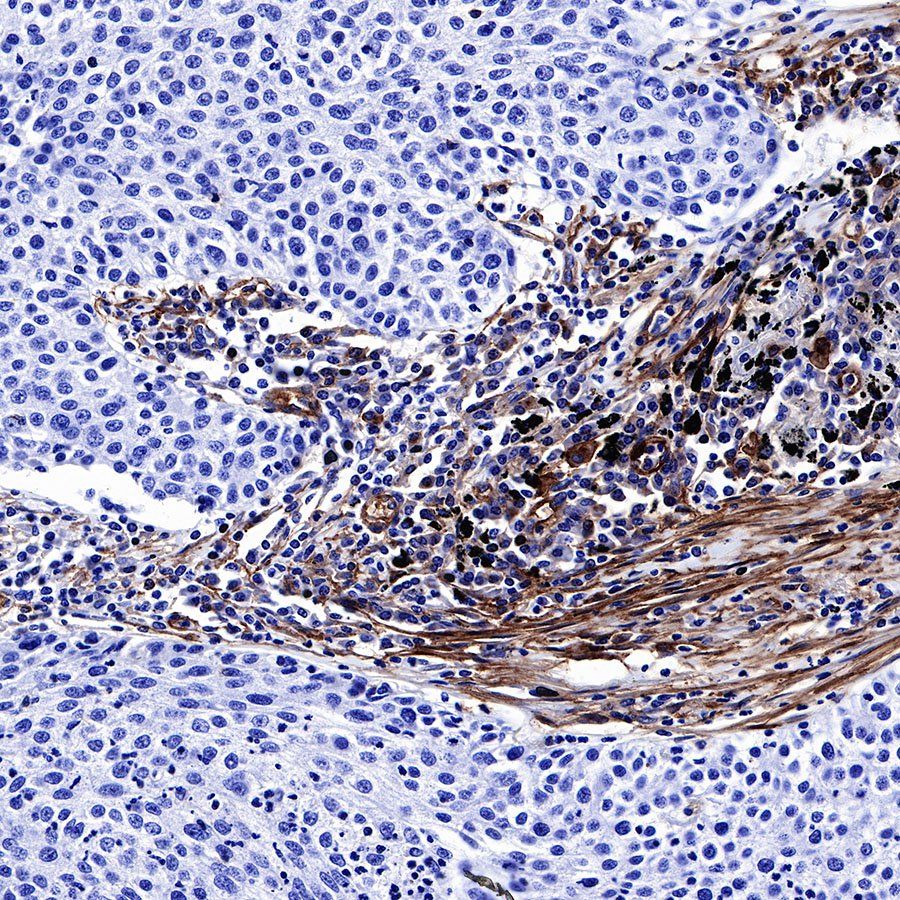

IHC shows positive staining in paraffin-embedded human placenta. Anti-CD39 antibody was used at 1/500 dilution, followed by a HRP Polymer for Mouse & Rabbit IgG (ready to use). Counterstained with hematoxylin. Heat mediated antigen retrieval with Tris/EDTA buffer pH9.0 was performed before commencing with IHC staining protocol.